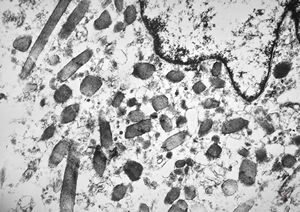

M,3y. | globoid leukodystrophy of Krabbe - n.suralis